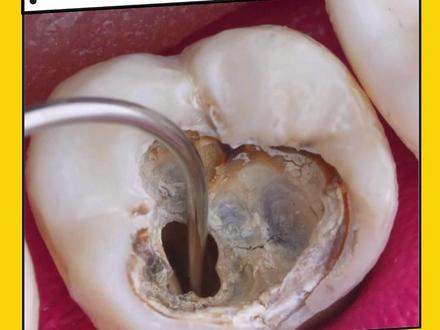

当你的牙齿腐烂到这种程度,就需要去做根管治疗了,那么你知道牙齿做根管治疗究竟有多酸爽吗?按照惯例,在手术开始前,牙医会在你的牙龈周围注射麻药,免得你待会疼的哇哇叫。但麻药生效后,牙医拿出高速打磨机,打磨掉取坏的牙釉质和牙本质, 虽说打了麻药一点都不疼,也不知道是真是假,此时你脑子除了嗡嗡的声音,还伴加了一股烧焦味, 而且打磨机在打磨的时候会放出高温,所以还要不断喷水降温,此时的你千万一定要忍住,不要吞口水。 一般在手术开始前,牙医都会在你口腔里面放一个吸引器,吸走多余的水分。清理完成后,牙医会在你的牙齿上套上一层无菌橡胶皮罩进行隔湿。 接下来就到了最酸爽的环节,牙医会拿出一根又细又长的孽太撮,对着你牙齿根管处不停的钻,将坏死的牙髓和牙神经清理干净,这酸爽感即便你是猛男也会流泪。最后再用生理盐水冲洗根管口,接着牙医会用干燥棒吸走根管口内残留的水分。 接下来就到了根管修复部分,牙医会用沾有根管封闭剂的牙胶尖插入根管内,再用加热棒溶掉多余的牙胶尖部分,再用修复树枝进行封边,再用紫外灯光固化。为了后面的牙齿填充更坚固,首先牙医会在你的牙齿上涂上一层蓝色的酸蚀剂, 其目的是使你牙齿表面更加的粗糙,方便后续填充材料更牢固。粘在牙齿上浸泡一会后冲洗干净,再涂上粘合剂,而粘合剂的作用是渗透到牙齿粗糙表面,再与之后填充的修复树枝发生粘结反应,从而将修复体与牙体组织牢固的连接在一起, 提升修复的稳定性和持久性。接着再逐层填充修复树枝,每填充一层要用紫外灯固化, 填充好的牙齿比较脆弱,牙医一般都会建议你将牙齿打磨小一圈,然后 再制作一个人工牙冠,相当于给你的牙齿穿上一层铠甲,从而提升其实用性。先在你的牙齿上面涂上一层硅橡胶来一膜,最后再送往牙齿加工室, 从而制造出一个属于自己的牙冠。确认无误后,用牙科粘接剂将牙冠永久粘固在预备后的牙体上,再用紫外灯固化,再刮去多余的粘接剂。最后看一下修复前后的对比图,这下知道爱护牙齿的重要性了吧!

当你的牙齿腐烂成这种程度,就建议去做根管治疗了,那么你知道牙齿做根管治疗究竟能有多酸爽吗?在手术开始前,牙医会在你的坏牙周围注射麻药,免得你待会疼的哇哇叫。待麻药生效后,牙医拿出高速打磨机, 对着你的坏牙部位一顿打磨,目的是去除上面已经坏掉的牙釉质和牙本质。在高速打磨过程中会产生热量, 因此还要不断喷水降温。经过一番的打磨,牙齿接近原本的颜色,就到了最酸爽的根管治疗环节。首先牙医会在你的坏牙上面套上一层无菌橡皮罩用来隔湿,再用打磨机将根管孔扩大,方便后续的根管治疗。 然后牙医拿出一根又细又长的镍钛错,对着根管口不停的钻,而镍钛错由钛合金制成,且钛的质地柔韧,富有弹性,形态与我们的根管高度贴合, 他一边在根管内旋转推进,一边就能将根管侧壁上附着的污物刮除干净。同时还要用生理盐水不断冲洗根管,冲走里面残留的碎屑。接着插入三根干燥棒,吸走根管内残留的水分。 接下来就到了根管修复阶段,插入三根沾有根管封闭剂的牙尖胶进行根管填充,再用加热工具溶掉多余的牙尖胶部分,再用加热工具压实,最后再用修复树枝封口,就可以用紫外灯光固化。接下来就是牙齿修复阶段, 牙医先会在你的牙齿周围涂上一层蓝色的酸蚀剂,其目的是在牙齿表面制作小凹槽,从而增加牙齿和补牙材料之间的附着力,浸泡一会,再用生理盐水清洗干净,最后涂上一层粘合剂,而粘合剂的作用试使修复材料更容易附着在牙齿上。 最后再用紫外灯进行光固,就可以逐层填充复合树脂材料。每填充一层复合树脂材料的时候,牙医都会使用光固化灯照射,使其迅速硬化。 而修复好的牙冠通常比较脆弱,牙医通常会建议你打磨小一圈,然后安装一个定制人工牙冠, 从而提升其使用寿命。而人工牙冠的作用就相当于给牙齿套上一层坚硬的盔甲。当牙齿打磨好后,牙医先会往你的牙齿上涂上一层硅橡胶,再用硅胶套在牙齿上, 等硅胶材料凝固后再将其取下,这样就得到了你牙齿的模型。确认无误后,牙医会将模型送到一尺加工厂,为你定制一个人工牙冠。 接下来就到了根管治疗的最后阶段,先在牙齿上涂上一层蓝色酸蚀剂,浸泡一会后,再用水冲洗干净,再涂上一层粘接剂。而蓝色酸蚀剂的作用是为粘接剂创造可附着的表面,使人工牙冠更加牢固的附着在你牙齿表面。 最后再将定制好的人工牙冠进行牙冠粘接,再用紫外灯光固化照射,刮去多余的粘接剂。至此,让人终身难忘的根管治疗就到此结束。最后看一下前后对比图,是不是舒服多了?